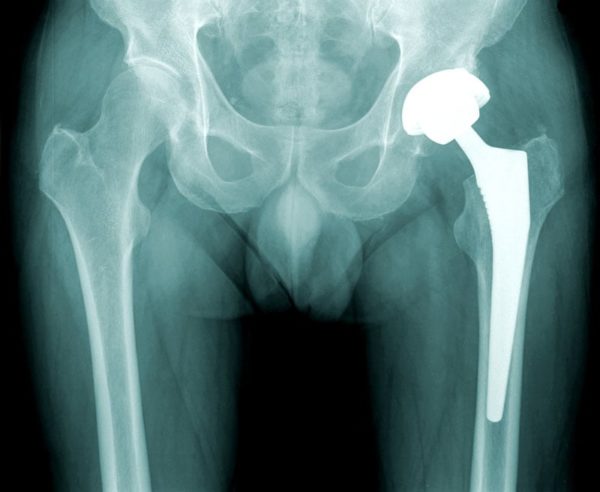

وتتم العملية بالقيام بتعقيم المريض وتجهيزه للعملية مع تخديره إما بمخدر موضعي مع منوم خفيف أو التخدير الكامل وهو أمر يحدده طبيب التخدير تبعاً لحالة المريض والوقت الذي ستستغرقه العملية.

تبدأ العملية من خلال قيام الجراح بعمل شقوق فوق الجزء الأمامي أو الجانبي من الورك من خلال طبقات الأنسجة، بعدها يتم إزالة العظام المريضة أو التالفة وكذلك الغضاريف مع ترك العظام السليمة دون المساس بها، ثم يقوم الطبيب بزراعة تجويف للأطراف الصناعية في عظام الحوض، لاستبدال التجويف التالف، وفي النهاية يتم استبدال الكرة المستديرة أعلى الفخذ بكرة صناعية والتي يجري تركيبها في الجذع المناسب في عظمة الفخذ.

يتم تعريف تلك العملية بأنها عملية جراحية يتم من خلالها استبدال مفصل الورك كاملاً بمفصل صناعي من المعدن أو البلاستيك، وتتم تلك العملية تحت تأثير التخدير النصفي لمنطقة الجراحة أو بالتخدير العام للجسم كله، إذ يكون المصاب عندها غائبًا عن الوعي، وتهدف إلى استبدال العظمتين التالفتين لخلق مُسطّحين جديدين في المفصل ليعمل المفصل أفضل، ويقوم الطبيب بتحديد طريقة التخدير المستخدمة بناءً على وضع المصاب، وحالته الصحية.